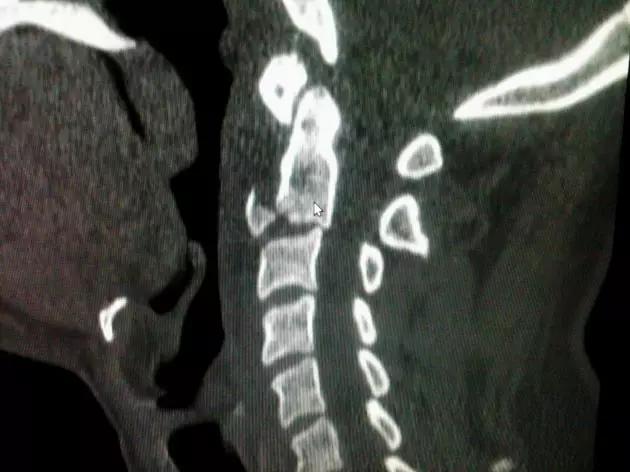

图为铲土者骨折(C3~C5)的平片(A)及 CT 扫描(B)(来源:Radiopaedia)